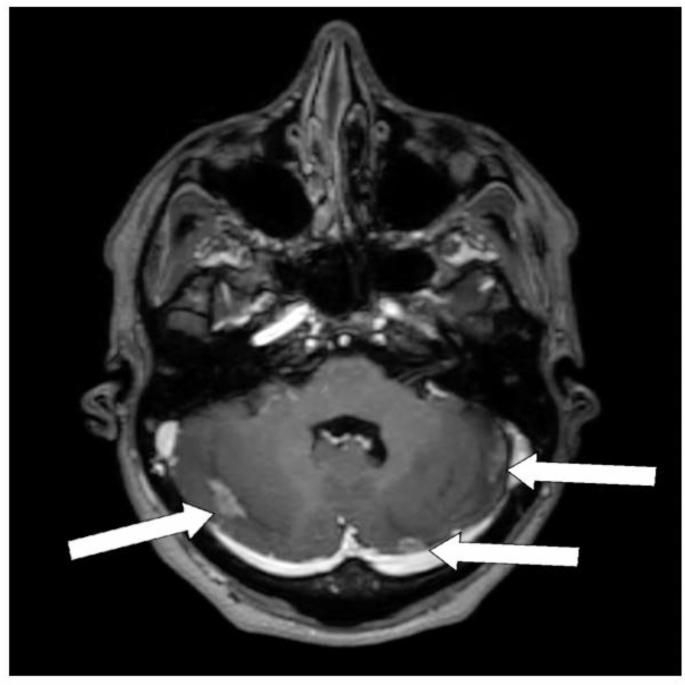

Breast cancer was the most common histology, affecting 40 patients. Other histologies included small cell lung cancer (8), ovarian adenocarcinoma (4), non-small cell lung adenocarcinoma (3), and melanoma (1). The median interval between WBRT and cerebellar RT was 15 months (range: 8–25). WBRT techniques included 3D planning in 85% of cases and VMAT with hippocampal avoidance in 15%. Most patients (92%) received 30 Gy in 10 fractions during WBRT, while the remainder received 20 Gy in 5 fractions (Figs. 1, 2 and 3).

Among the 56 patients who underwent re-irradiation to the cerebellum, only one developed symptomatic radiation necrosis (RN), representing 1.7% of the cohort. This patient was a 44-year-old woman diagnosed with breast cancer. She had previously received WBRT with a dose of 30 Gy in 10 fractions using a 3D technique.

Five months later, due to progressive symptomatic disease in the cerebellum, she received a second course of 25 Gy in 5 fractions using VMAT approach.

Five months following the second RT course, she presented with headaches and vomiting. Follow-up MRI revealed significant edema and a reduction in the size of the metastatic lesions. Multi-parametric MRI, including a TRAM sequence, suggested RN, which was confirmed in a tumor board discussion. Her dexamethasone dosage was increased to 16 mg twice daily, resulting in relief of her symptoms within three weeks. Unfortunately, despite symptomatic management, the patient succumbed to progressive systemic disease eight months after the second RT course.